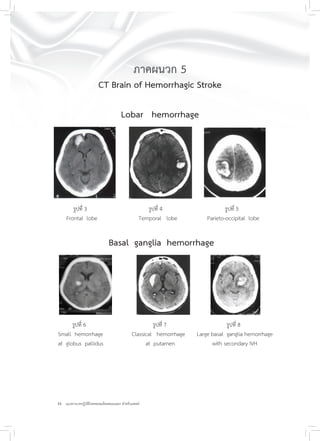

ภาคผนวก 5

CT Brain of Hemorrhagic Stroke

Lobar hemorrhage

รูปที่ 3 รูปที่ 4 รูปที่ 5

Frontal lobe Temporal lobe Parieto-occipital lobe

Basal ganglia hemorrhage

รูปที่ 6 รูปที่ 7 รูปที่ 8

Small hemorrhage Classical hemorrhage Large basal ganglia hemorrhage

at globus pallidus at putamen with secondary IVH